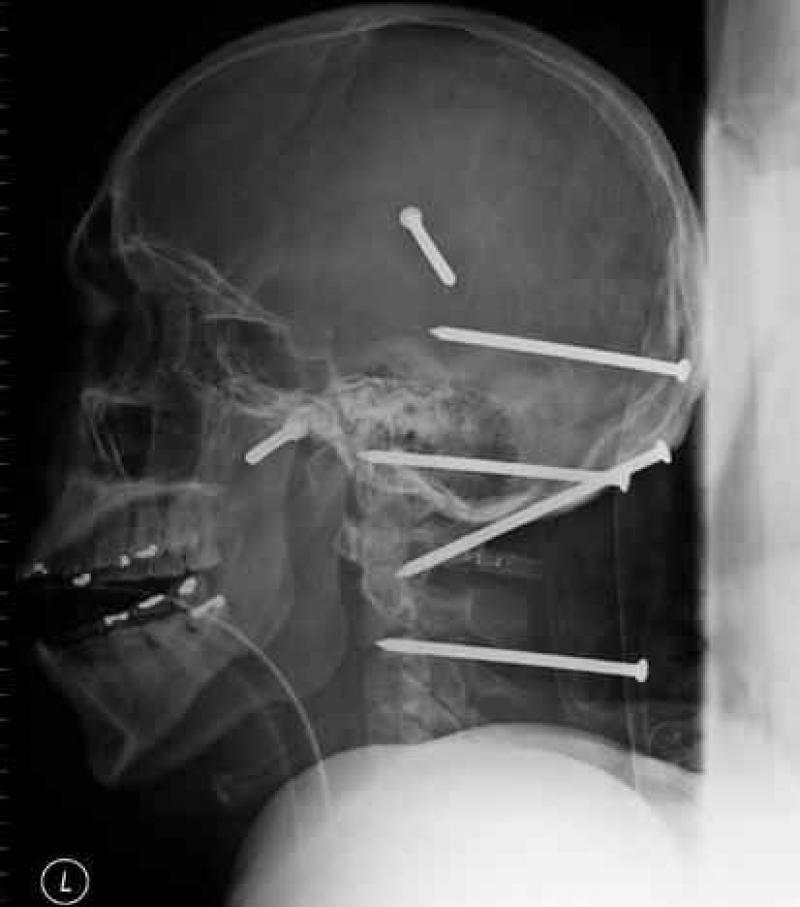

Röntgenfoto's zijn een medische uitvinding die ons al decennia lang helpt. Ze geven een nieuw gezichtspunt als het gaat om het vinden en behandelen van inwendige verwondingen. De machines kunnen opmerkelijke beelden vastleggen van het menselijk lichaam en ze documenteren vaak gruwelijke verwondingen. Een wonde van iemand zien, is al erg, maar als je ook kan zien wat de schade in het lichaam is, dat is nog veel erger. We hebben 12 tegelijk fascinerende, gruwelijke en hilarische röntgenfoto's op een rijtje gezet. Stel jezelf maar eens de vraag hoe iemand ooit aan die verwondingen is gekomen. We beginnen nog rustig.